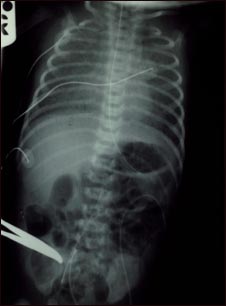

Retorno venoso pulmonar total anómalo, rayos X

El retorno venoso pulmonar totalmente anómalo es una forma de enfermedad cardíaca congénita.